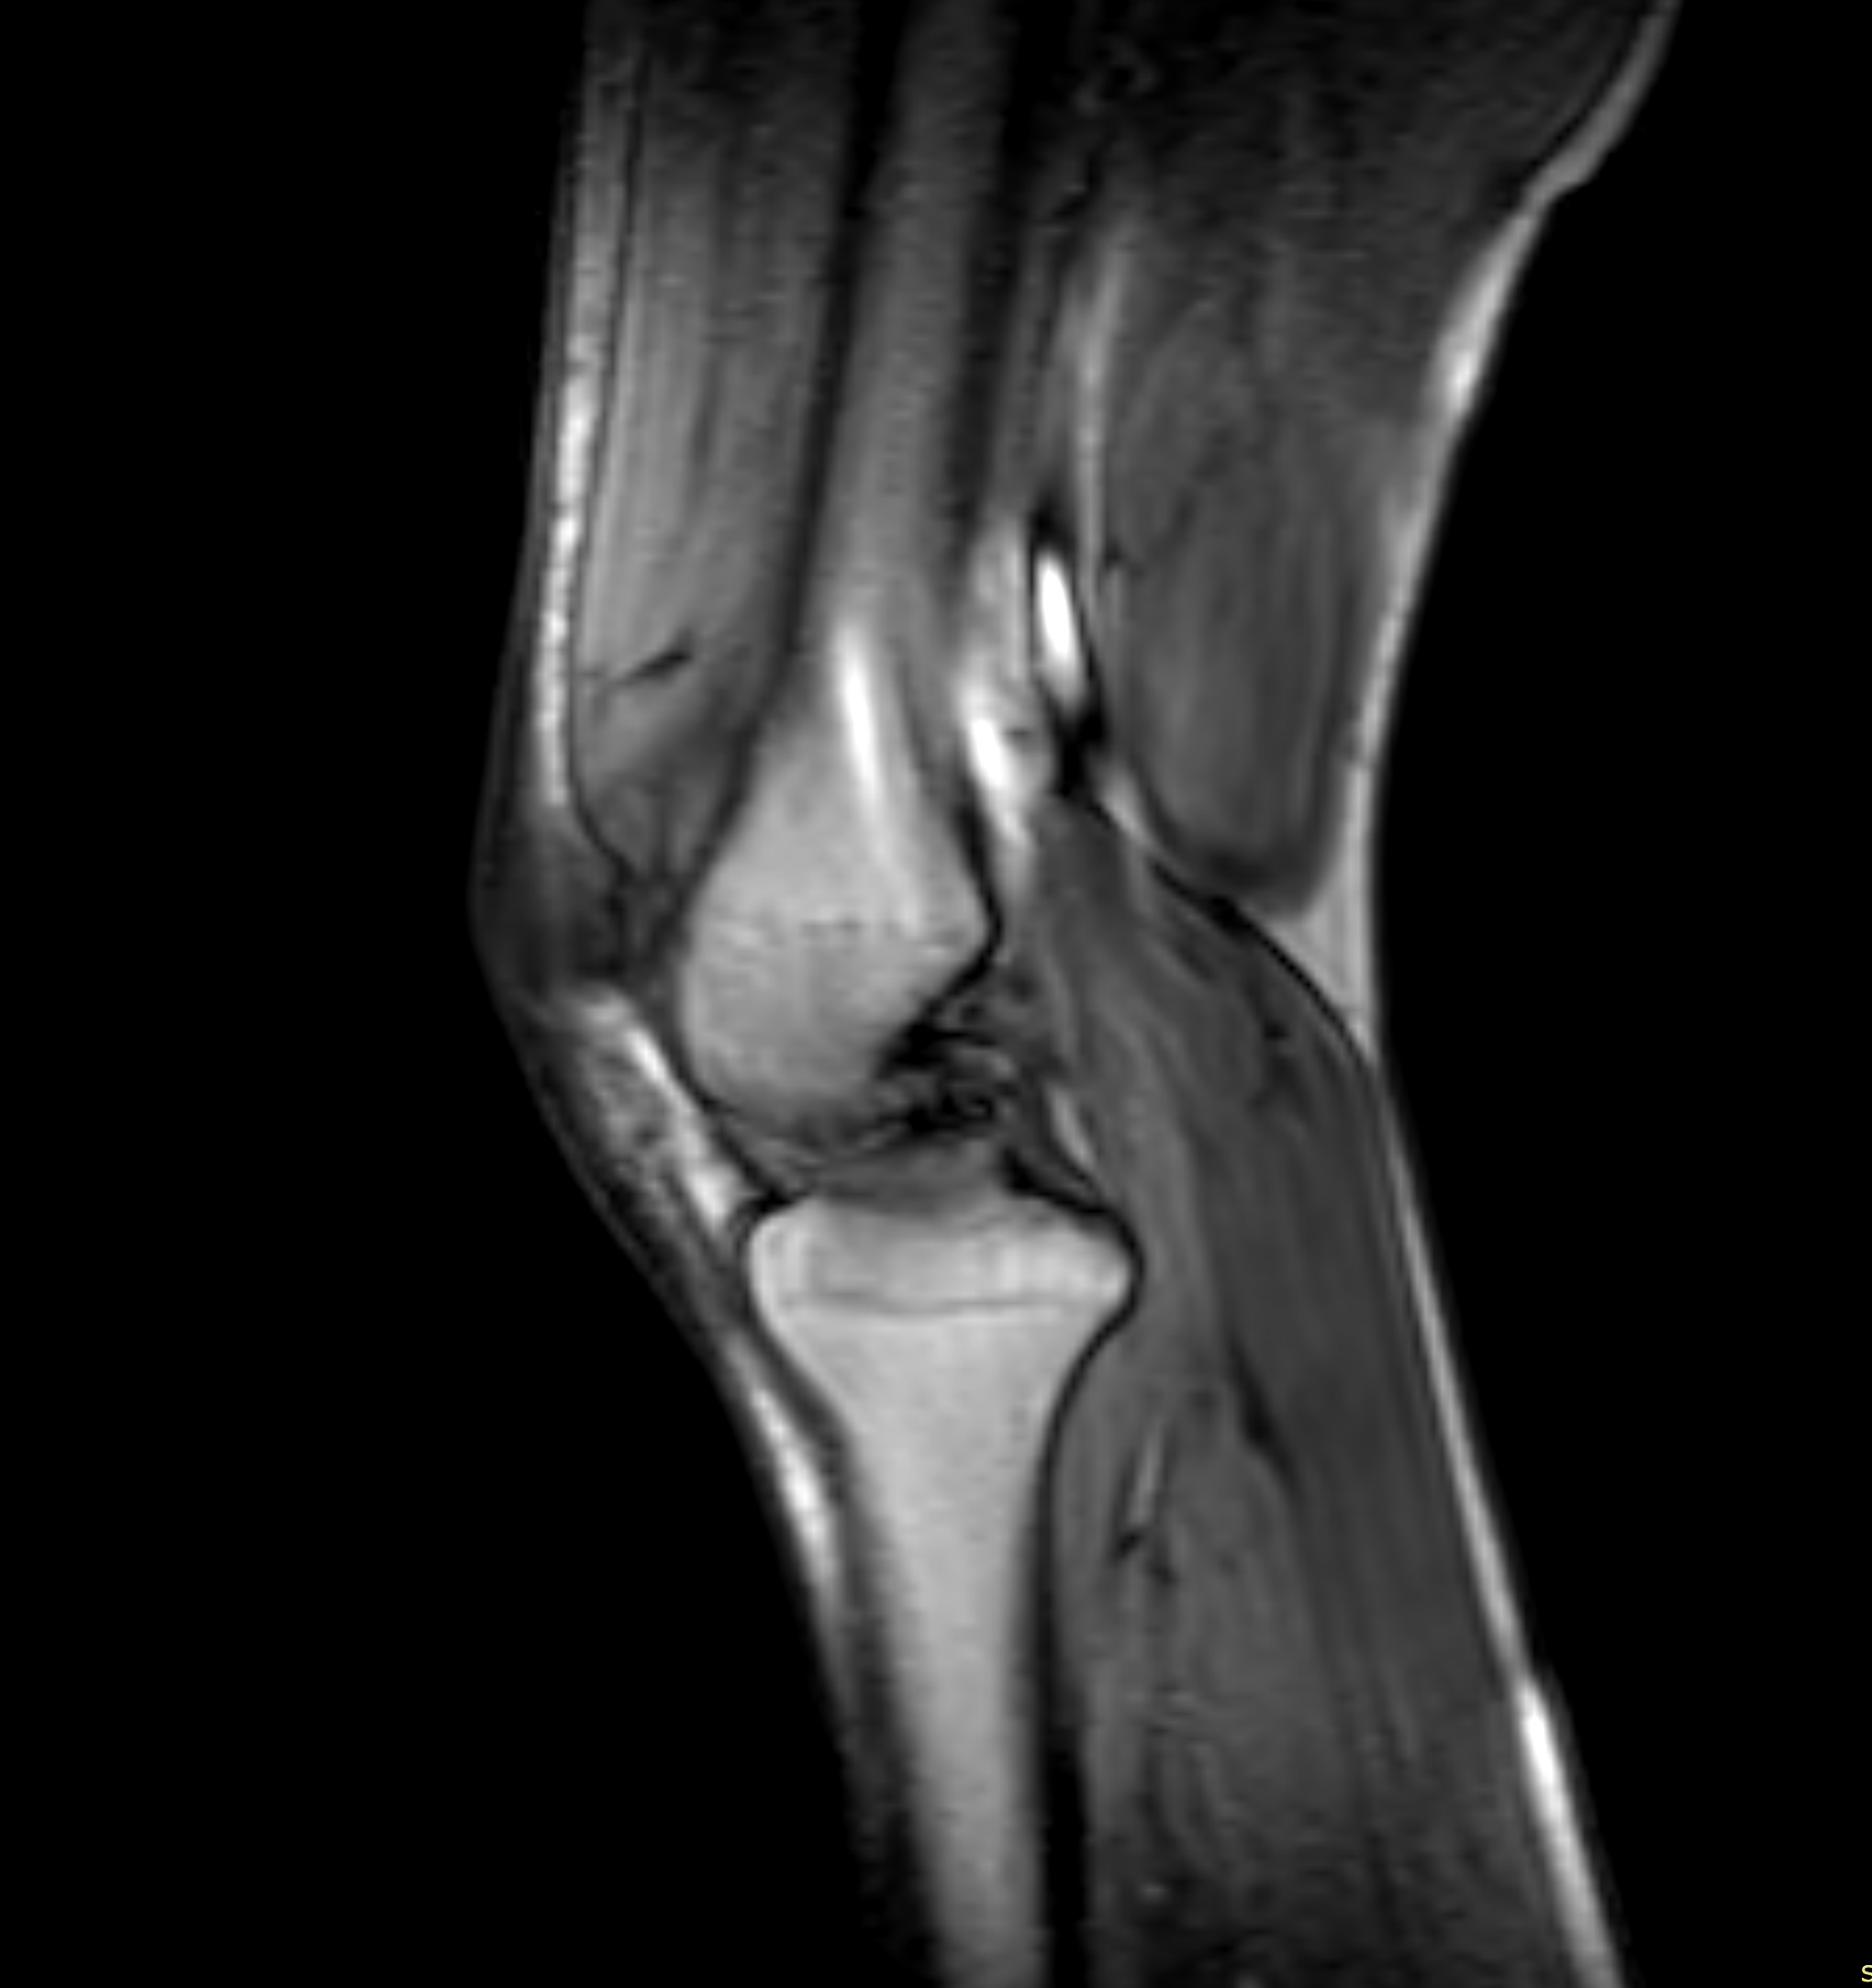

Knäleden är kroppens största och mest belastade led – en komplex struktur av ben, brosk, ledband, menisker, senor och slemsäckar som tillsammans möjliggör rörelse, stabilitet och stötdämpning. Det gör knäet särskilt utsatt för både akuta skador och förslitningar. Med en magnetkameraundersökning (MR) av knä eller knäled får man en mycket detaljerad bild av både skelett och mjukdelar. Undersökningen är helt utan strålning, smärtfri och överlägsen andra metoder när det gäller att upptäcka meniskskador, korsbandsskador, broskförändringar, artrit eller seninflammation.

MR-undersökning av knät är särskilt värdefull i flera kliniska situationer. Om du står inför en planerad operation – exempelvis vid misstänkt menisk- eller korsbandsskada – ger en MR en noggrann kartläggning av strukturerna i knäet, vilket är avgörande för korrekt kirurgisk planering.

Undersökningen är också viktig när tidigare bilddiagnostik, som slätröntgen eller ultraljud, inte gett tillräcklig information. Det gäller särskilt vid mjukdelsskador, broskförändringar eller svårbedömda smärttillstånd där man misstänker en dold skada.

- Främre eller bakre korsbandsskada (ACL/PCL) – Vanlig vid idrottsskador. MR är den bästa metoden för att visualisera om ledbandet är uttänjt, delvis brustet eller helt av.